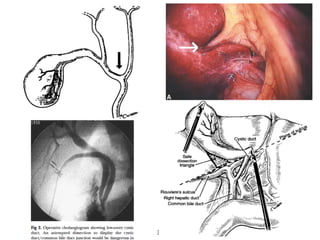

Guias para la reparación de la lesión de la VB

1. Exponer el área dañada evitar la disección sobre

extendida

2. El muñón del conducto lesionado debe estar libre de

quemaduras y estrechez

3. Colangiografia transoperatoria para detectar fuga biliar

4. La integridad vascular debe ser confirmada

5. Hepaticoyeyunostomia con Asa en Y de Roux

6. Oposición de ambas mucosas con hilo absorbible

7. Uso de magnificación

53

Manejo de la Lesión Quirúrgica de la VB

Anastomosis Hepp-Couinaud

•

Disección de la placa

• Lazo al cilindro hiliar

• Decolamiento:

• Incisión hacia la incisura

vesicular y posterior, y luego

hacia la umbilical

• Palpación del hilio

• Colecistectomia, disección del T.

Calot y pedículo hep. derecho

Maniobra de

Hogart-Pringle

• Disección de la placa

• Descenso de la placa: roma y el hígado arriba

• La rama biliar izq. desciende extrahepática

• Horizontal, constante y superficial

• Comprobar la indemnidad de invasión neoplásica

• Toda la rama izquierda expuesta en su penetración

en el ángulo postero-izquierdo del lob. cuadrado